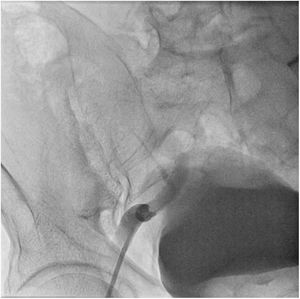

El paciente se traslada a la sala de hemodinamia donde se intenta la extracción del dispositivo. Se utilizan diferentes catéteres lazo de 10, 25 y 30 mm, así como lazos de fabricación con guías largas y cortas intentando movilizar el dispositivo desde diferentes accesos vasculares (acceso bifemoral 6 y 18 Fr y radial 6 Fr) (figuras de la 1 a la 4). Se produce como complicación disección de aorta abdominal con extensión a arteria ilíaca común derecha (figuras 5 y 6) y pérdida total del flujo en extremidad inferior ipsilateral con signos y síntomas de isquemia arterial aguda, por lo que el paciente es trasladado de forma urgente al quirófano de angiología y cirugía vascular. Se realiza disección de aorta abdominal infrarrenal vía laparotomía media con aortotomía longitudinal en el lugar de la localización del cuerpo extraño visualizándose el dispositivo migrado anclado a la íntima-media de la pared arterial. Se procede a su extracción y posteriormente se realiza cierre de aortotomía con parche de pericardio bovino fijando la disección y corrigiendo así el defecto (figuras de la 7 a la 9). El paciente sale de quirófano con pulso pedio bilateral y excelente perfusión distal.